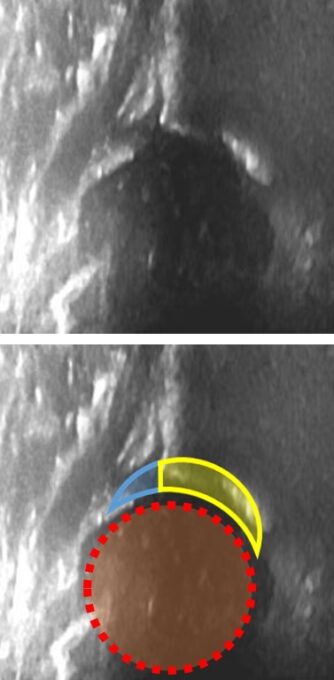

11. グラフ(Graf)法について

グラフ法による標準画像から5つに分類され、下3つでは治療が必要です。正常と脱臼とでは全く見え方が違うので、エコー〈超音波)検査で正常だった乳児の中から脱臼が生じることない信頼性の高い検査法です(新生児でも症例報告となるほど稀です)

正常![]() |

脱臼(グラフ分類3型)![]() |

| 全く違う像なので見間違えがありません | |